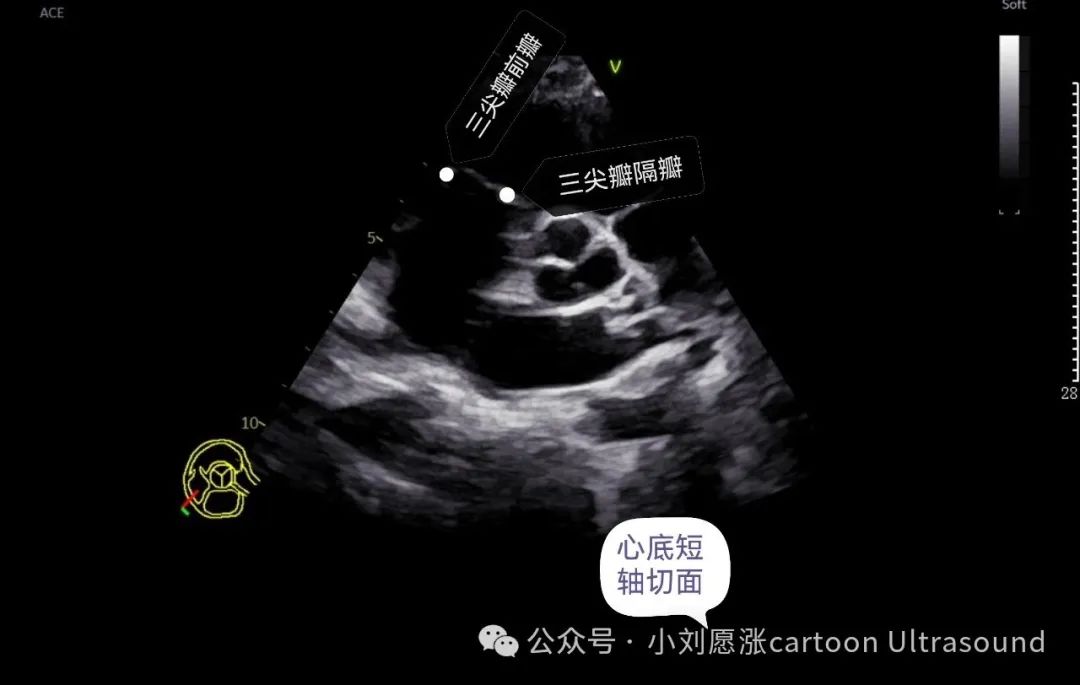

三尖瓣:3个瓣叶,前瓣、后瓣、隔瓣,后瓣只能右室流入道切面观察‍‍‍‍。

主动脉瓣:3个瓣叶,右冠瓣、左冠瓣、无冠瓣, 心底短暂切面 注意观察瓣叶个数,二叶是主动脉瓣畸形最多见。